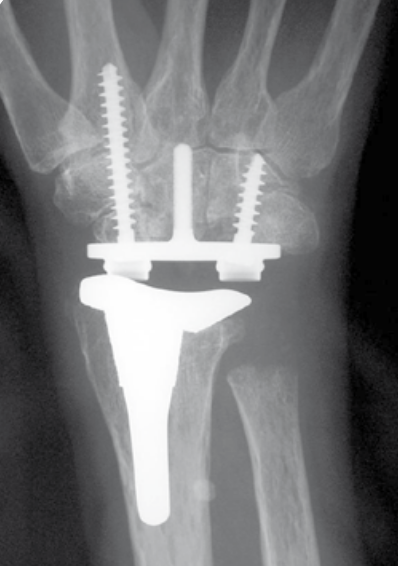

Total wrist arthroplasty

Technique

Universal TWAUniversal 2 TWA

Dorsal approach

- incision in line with 3rd meta-carpal

- divide extensor retinaculum over ECU compartment and reflect radially

- mobilize entensor tendons

- ensure ECRB and ECRL intact

- elevate wrist capsule as a distally based flap

TWA

- uncemented radial prosthesis

- excise lunate and apply carpal cutting block to capitate

- cut 1 mm hamate / capitate head / midscaphoid

- screw fixation of carpal plate

- trial polyethylene component

Results

Wagner et al CORR 2017

- 425 primary total wrist arthroplasty followed for mean 2 years

- 90% inflammatory arthritis

- intra-operative fractures 2%

- postoperative fractures 2%

- 88% 10 year survival